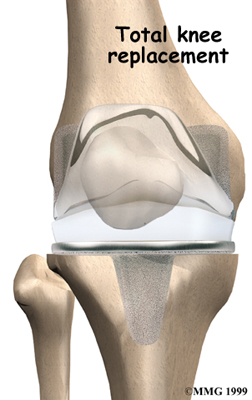

Artificial Knee Replacement

An artificial knee replacement is the ultimate solution for advanced knee OA.

Surgeons prefer not to put a new knee joint in patients younger than 60. This is because younger patients are generally more active and might put too much stress on the joint, causing it to loosen or even crack. A revision surgery to replace a damaged prosthesis is harder to do, has more possible complications, and is usually less successful than a first-time joint replacement surgery.

Related Document: FYZICAL Lake Charles Guide to Artificial Joint Replacement of the Knee